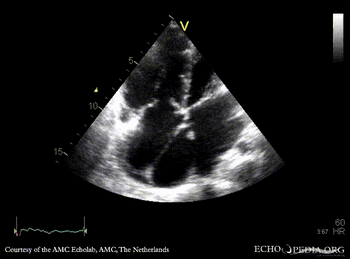

Cor triatriatum dextra

A4CH: Cor triatriatum dextra A4CH: Color Doppler: moderate tricuspid regurgitation